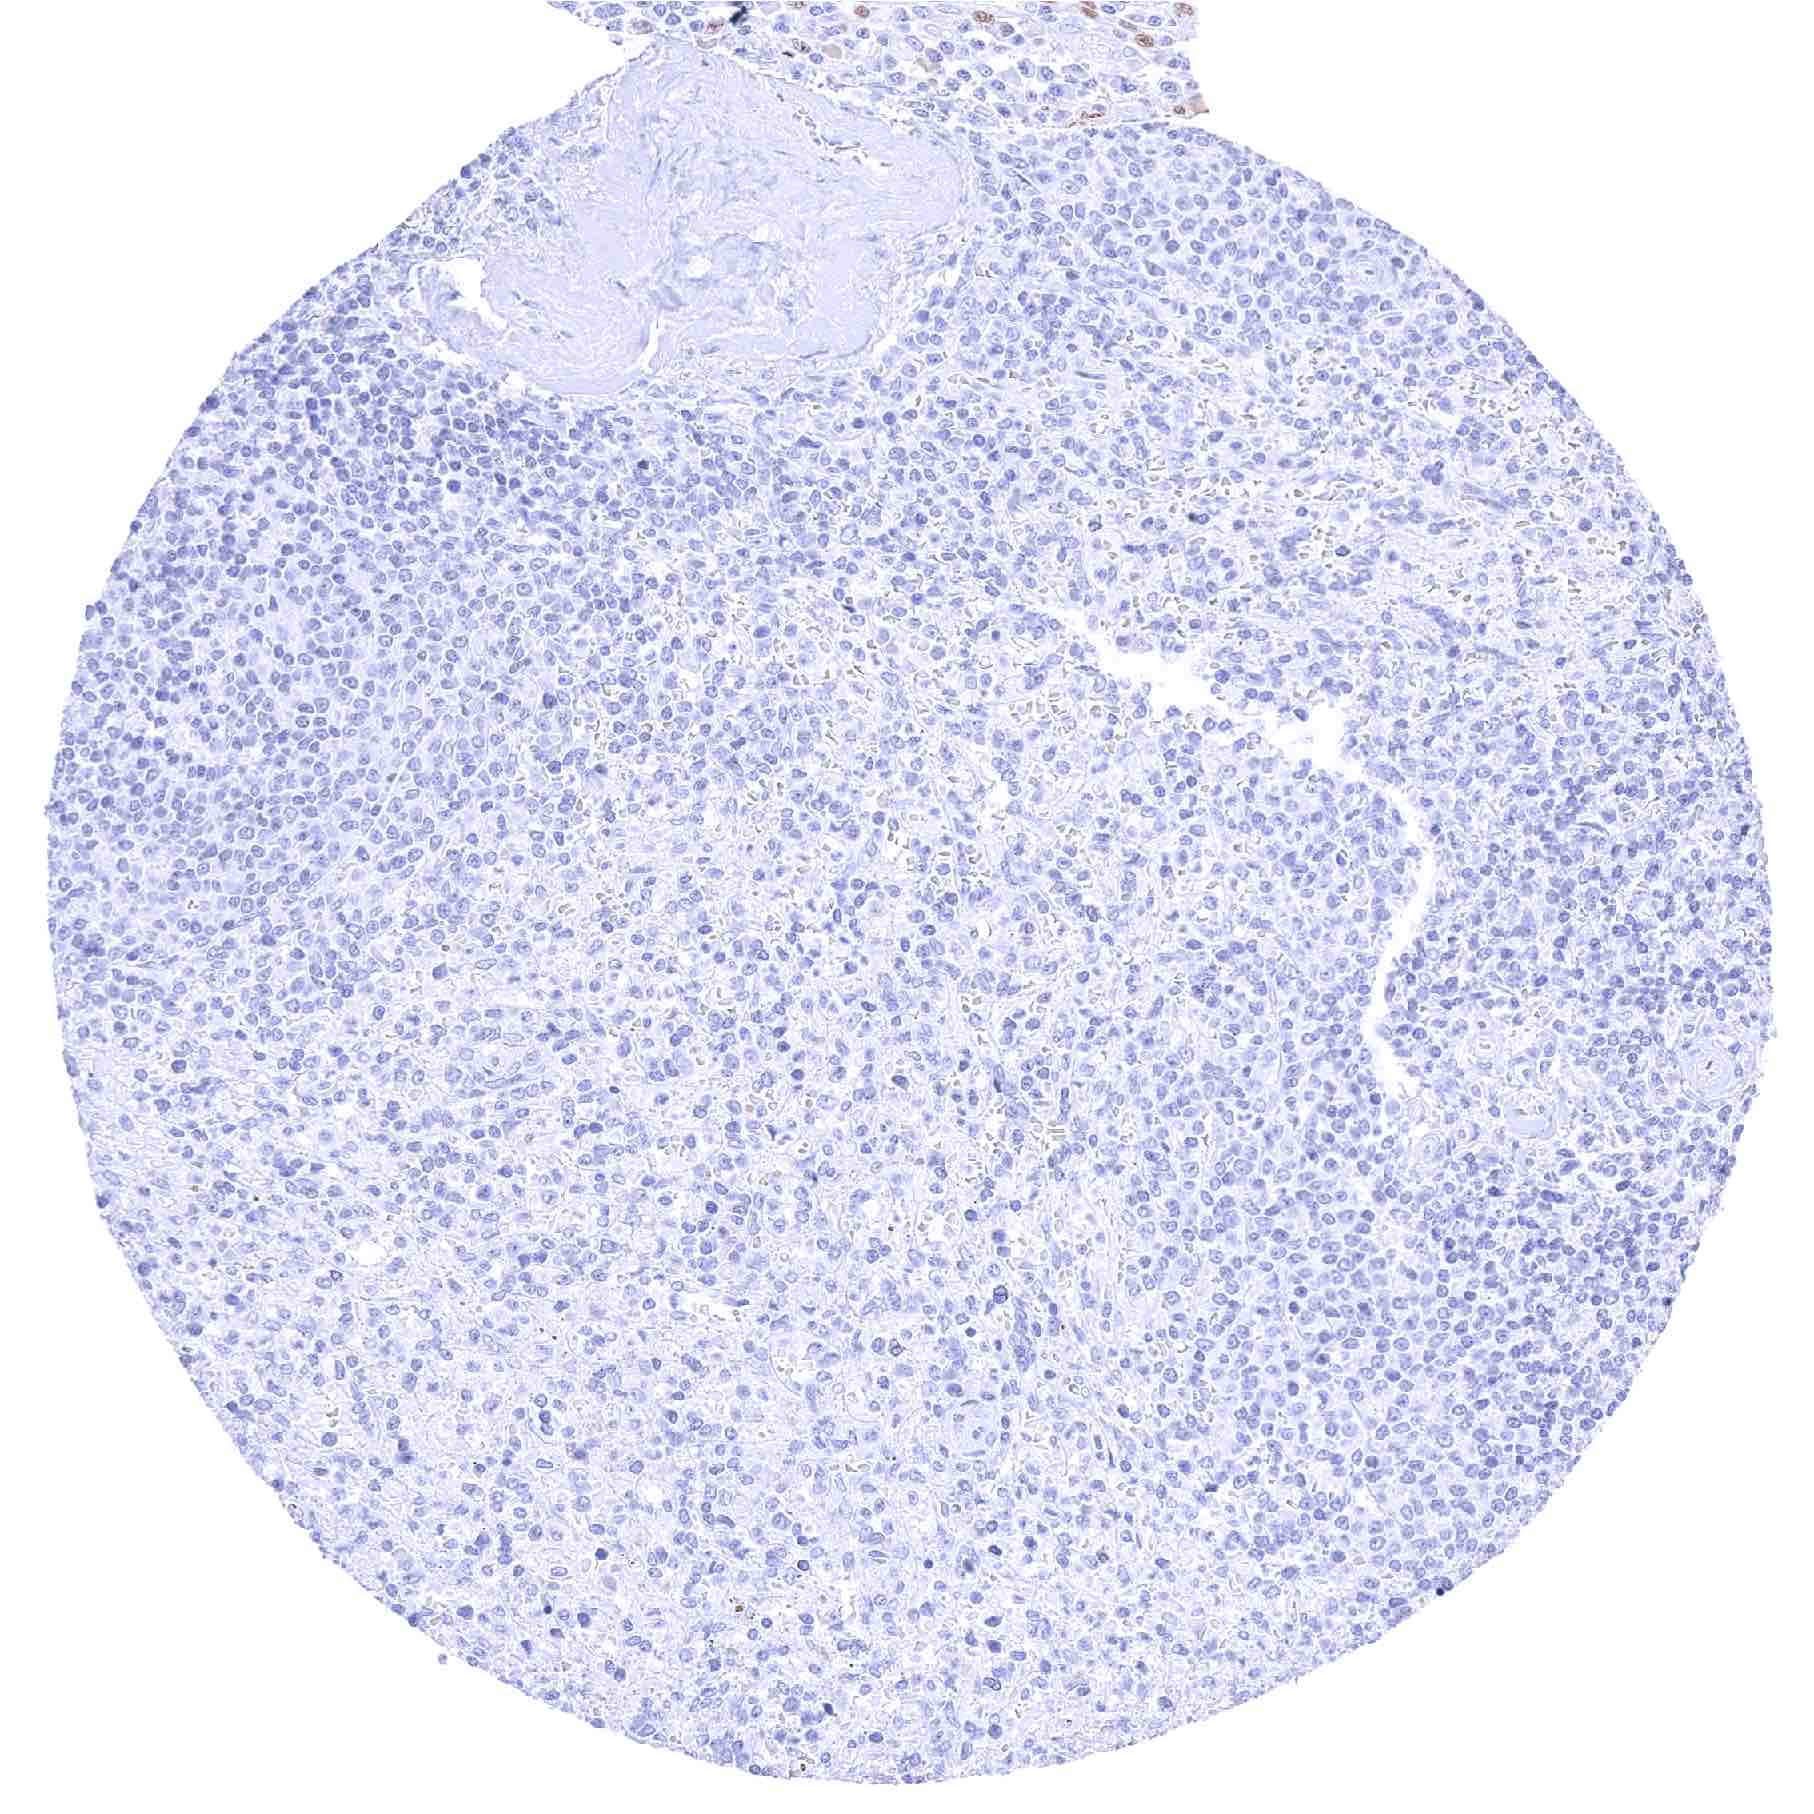

Lymph node